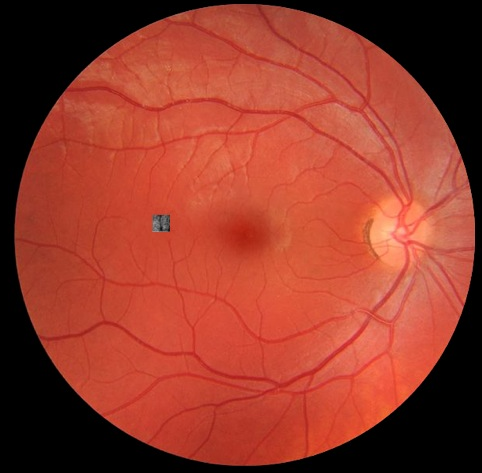

Fig. 2 shows the typical size of an AO corrected image on the retina. With a conventional AO correction, the resulting image covers a maximum of on the retina. Several techniques aim at increasing this field of view. One such technique is called star-oriented multi-conjugate approach. It permits to correct images within fields. Muti-conjugate AO comes in two flavors. Today we will suggest the use of the second flavor – the layer oriented approach. We believe that this shall permit to increase the size of AO corrected images to .

One method for wide-field AO imaging relies on the use of a scanning mirror. The individual AO corrected images are small, but a series of images is recorded and are then stitched together to yield one large, high-resolution image. The images in Fig. 3 are wide. This method is simple and efficient, but it encounters practical limitations. An imaging session lasts typically one hour and this excludes the examination of young patients. Also, the reconstruction of a large image from a series of small images is not straightforward: ideally, the patient’s visual fixation should be perfectly steady over all acquisitions. Large variations in the fixation lead to artifacts in the image reconstruction. This is a particular difficulty for patients with visual impairment, but variations occur even in healthy eyes, when the subject is trying to maintain a steady fixation.